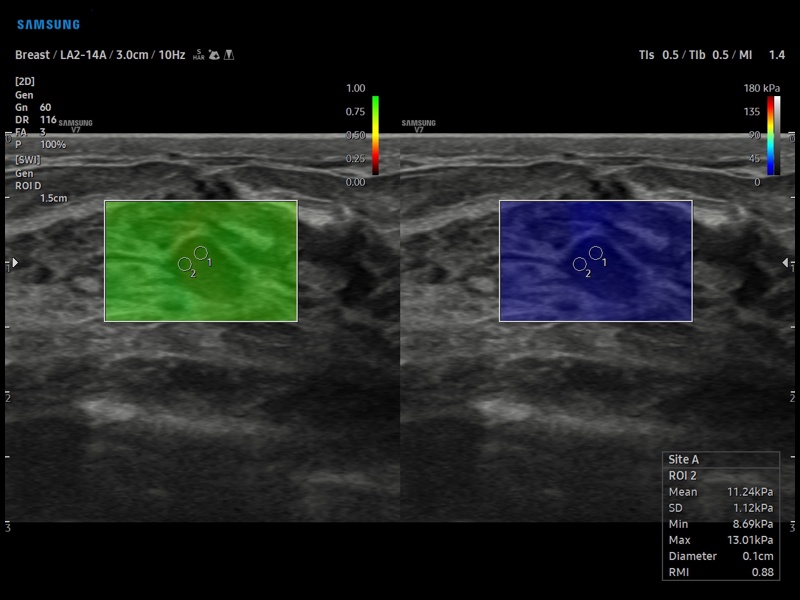

[RU] Ultrasound image №898: Breast in S-Shearwave™ mode - shear wave elastography (linear probe 2-14 MHz).

Echogramm was received by ultrasound scanner V7 (available for sale).